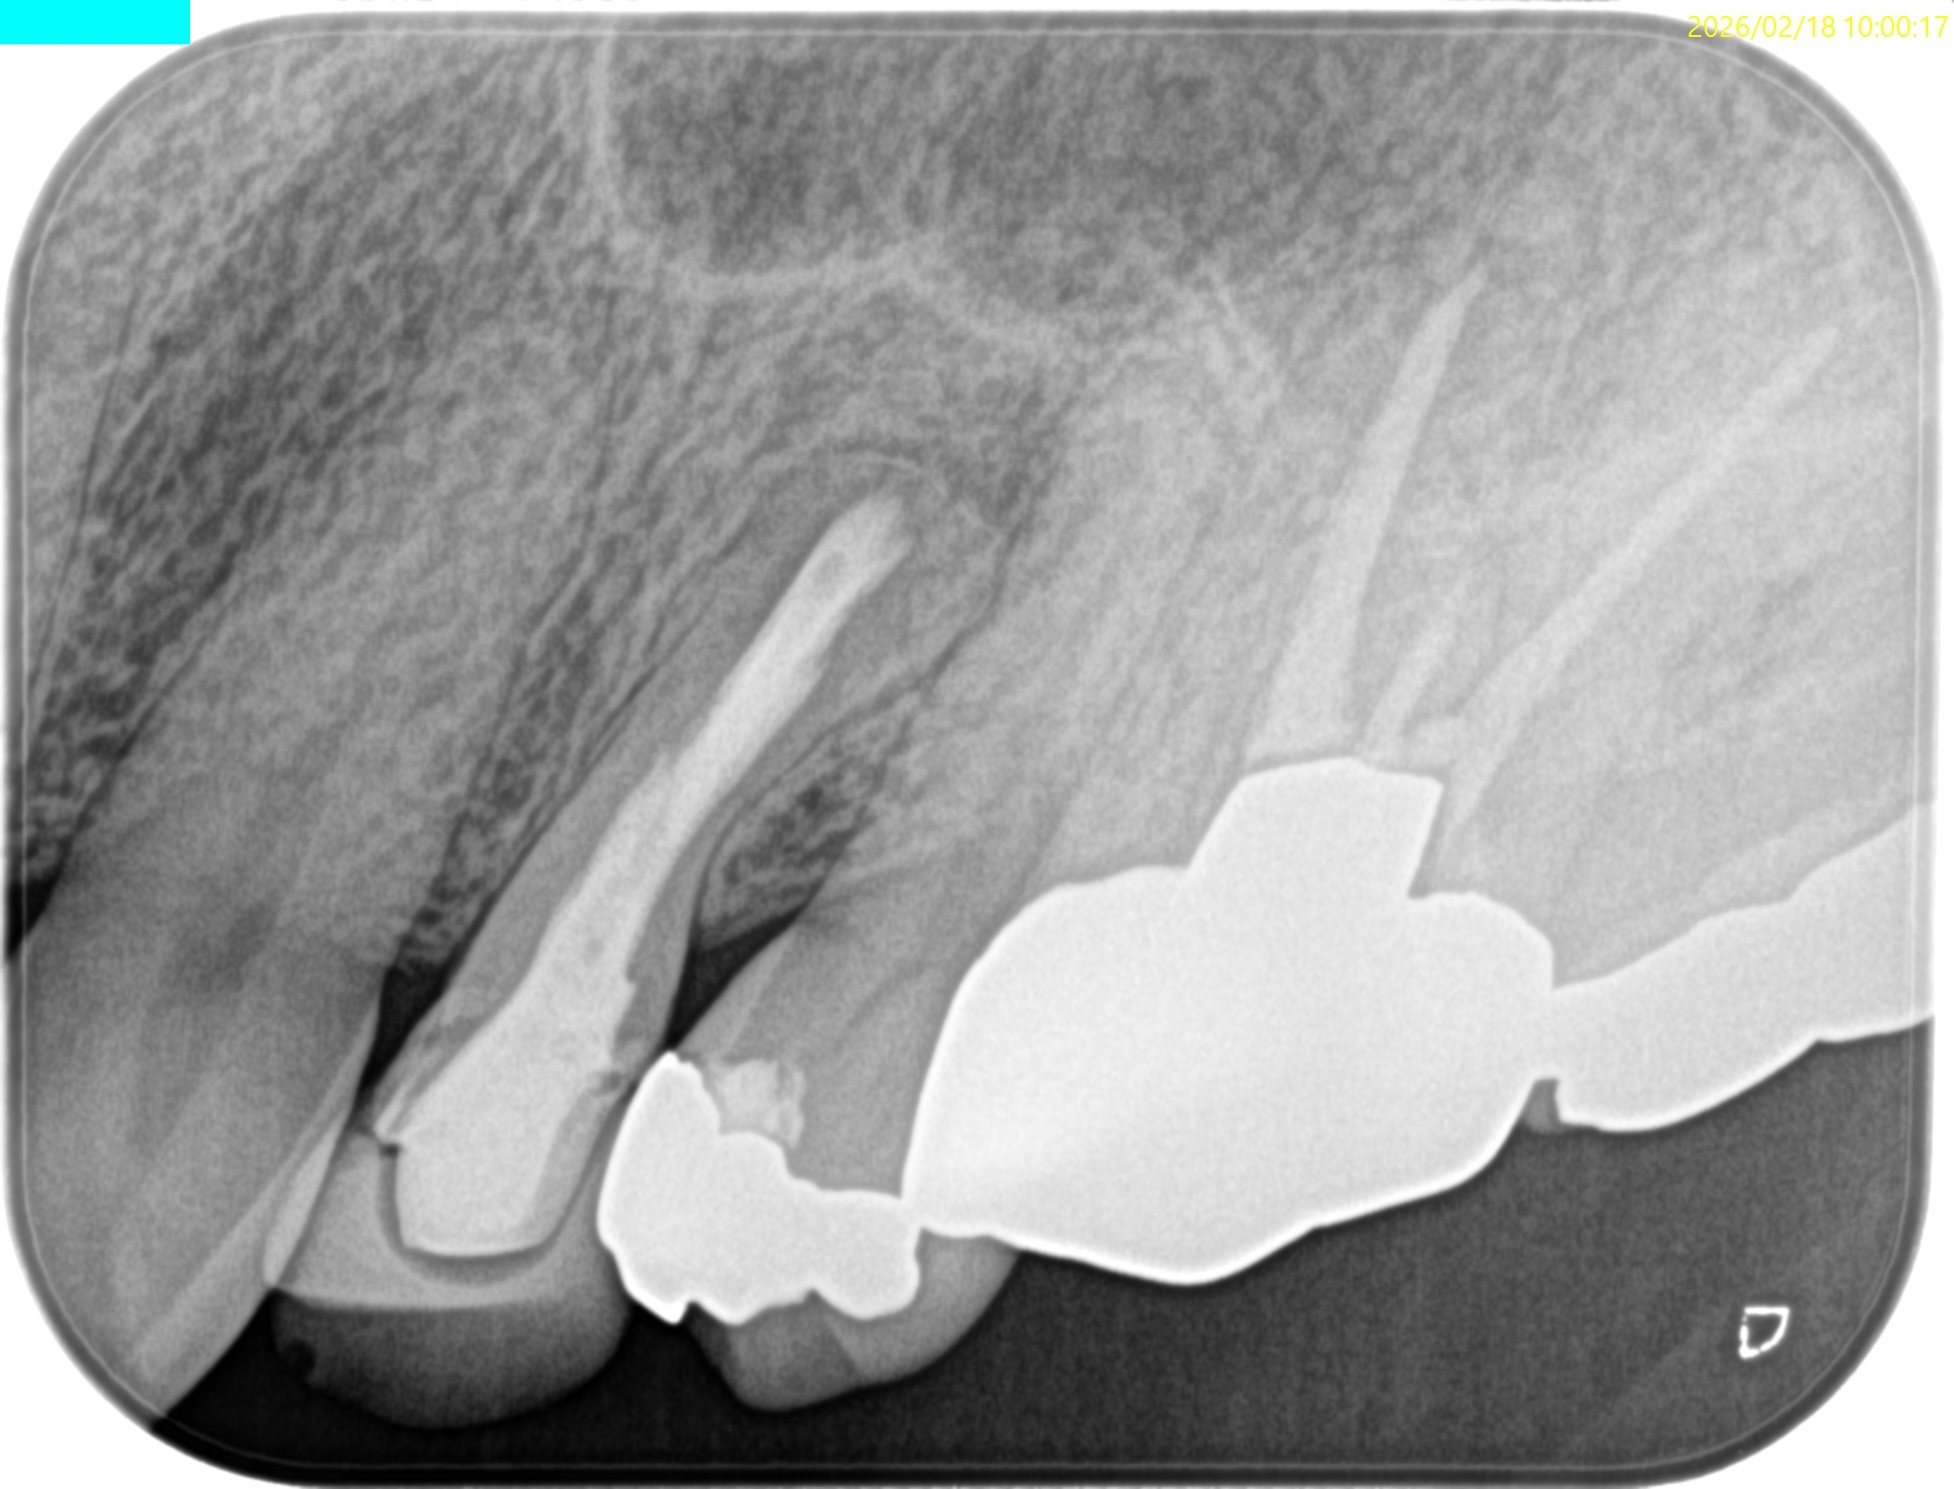

#12 Apicoectomy 6M recall(2026.2.18)

初診時と比較した。

問題は大きく解決している。